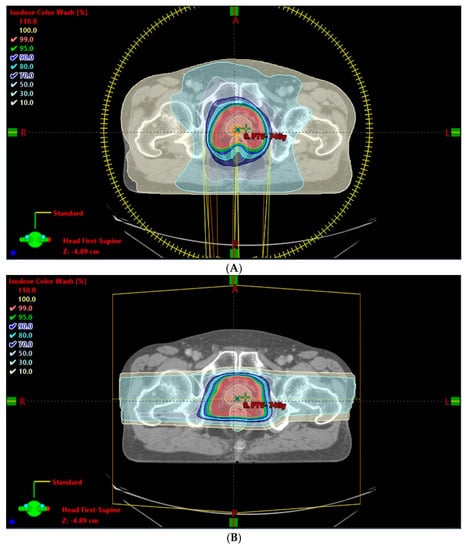

- Chung, H.; Polf, J.; Badiyan, S.; Biagioli, M.; Fernandez, D.; Latifi, K.; Wilder, R.; Mehta, M.; Chuong, M. Rectal dose to prostate cancer patients treated with proton therapy with or without rectal spacer. J. Appl. Clin. Med. Phys. 2016, 18, 32–39. [Google Scholar] [CrossRef]

- Polamraju, P.; Bagley, A.F.; Williamson, T.; Zhu, X.R.; Frank, S.J. Hydrogel spacer reduces rectal dose during proton therapy for prostate cancer: A dosimetric analysis. Int. J. Part. Ther. 2019, 5, 23–31. [Google Scholar] [CrossRef] [PubMed]

- Dinh, T.-K.T.; Lee, H.J.; Macomber, M.W.; Apisarnthanarax, S.; Zeng, J.; Laramore, G.E.; Rengan, R.; Russell, K.J.; Chen, J.J.; Ellis, W.J.; et al. Rectal hydrogel spacer improves late gastrointestinal toxicity compared to rectal balloon immobilization after proton beam radiation therapy for localized prostate cancer: A retrospective observational study. Int. J. Radiat. Oncol. 2020, 108, 635–643. [Google Scholar] [CrossRef] [PubMed]